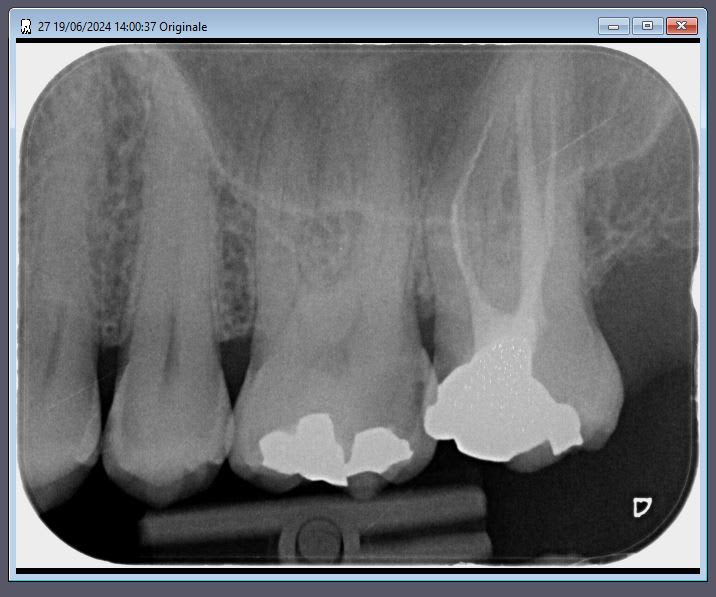

19/06/2024 à 14h13

pas besoin de faire de l'elitisme...

la par exemple un atient de 40 ans a l'instant, je pense pas reprendre l'endo de 27...

mais je pense remonter les marges 27 26 au cvi et reconstituer 27 26 25 en stratifictaion sous digue...

bin pas au tarif secu... ca suffit.

et celui qui a traité initialement 27 26 bin c'est pas bravo. et je me considere comme pas bon... et encore la c est de l amalgame... quand c est du compo c est pire.

Prunelles, tu ferais quoi ici ?

Mon plan de traitement pour ton cas : compo 25, inlay ou onlay emax sur 26 et adressage à l'endo exclusif pour 27 avec gros onlay ou couronne à suivre (la radio ne me suffit pas).

19/06/2024 à 15h41

> Mon plan de traitement pour ton cas : compo 25, inlay ou onlay emax sur 26 et

> adressage à l'endo exclusif pour 27

oui c est ce qu il faudrait faire.